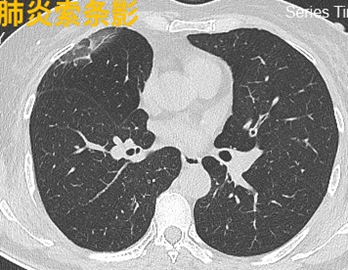

(4)肺炎性纤维灶:指慢性炎性病变愈合后遗留的瘢痕组织,正常人CT检查经常发现。